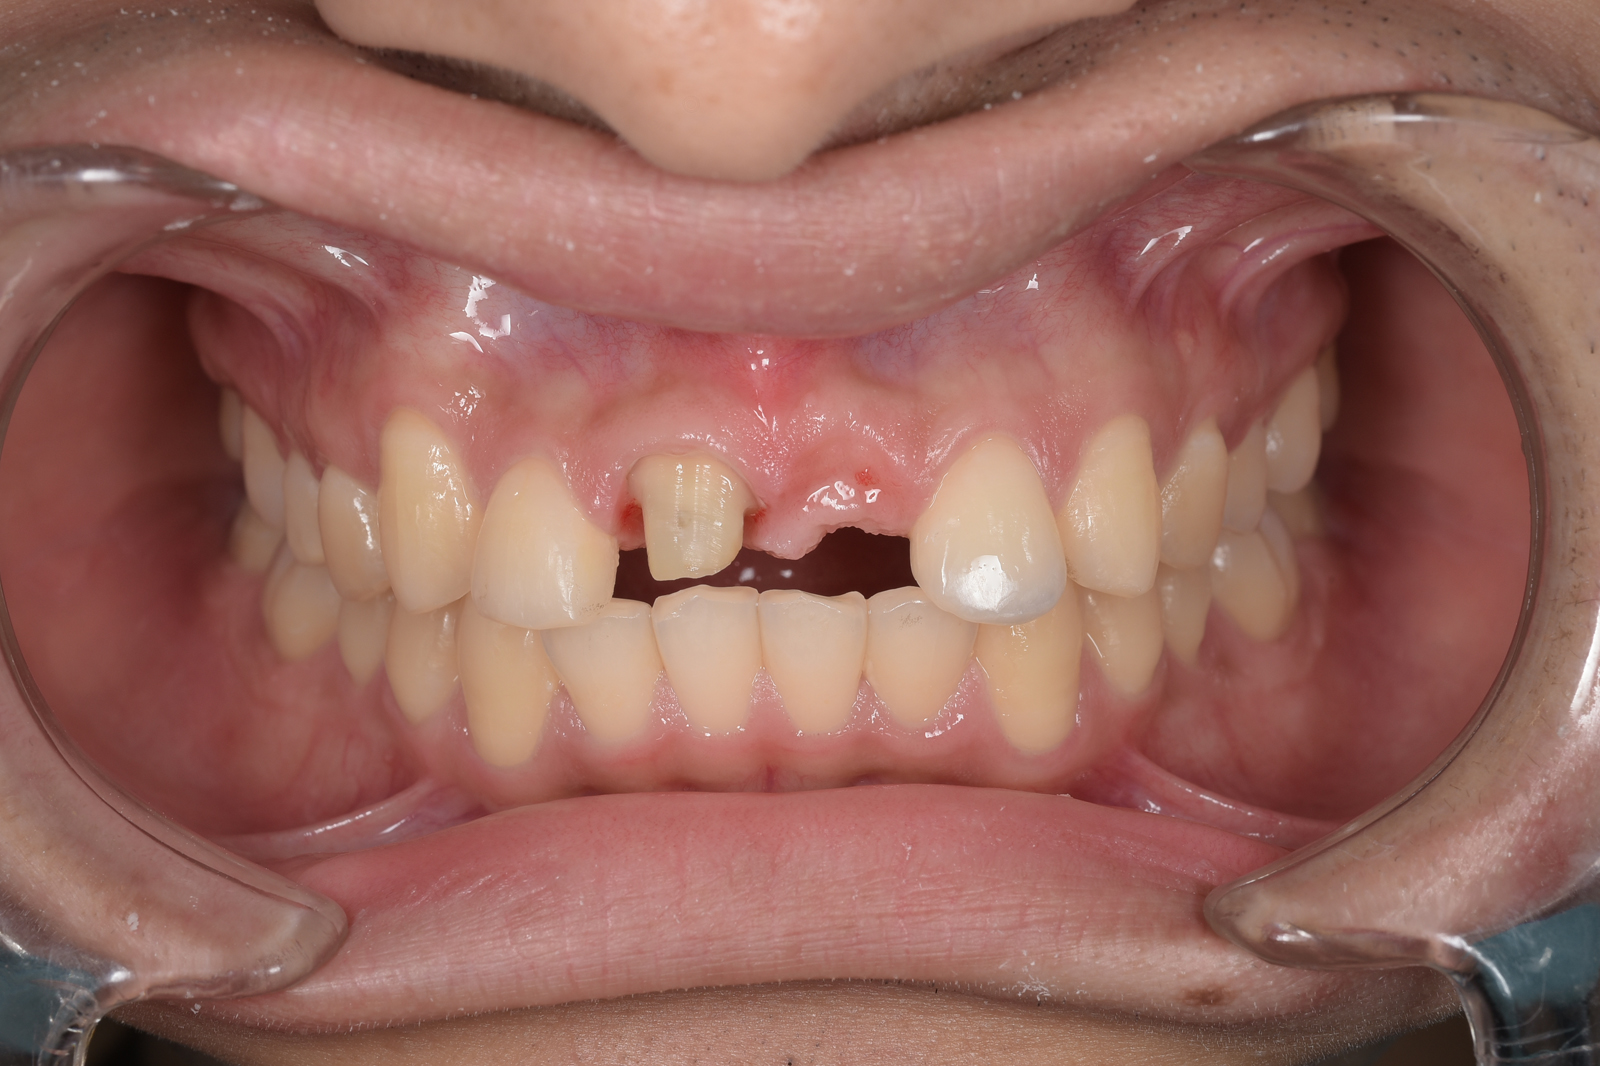

重度の虫歯で失われた、上あごの前歯を治療した症例。